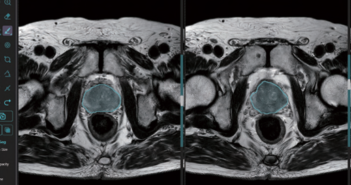

의료 AI 1호 상장기업 제이엘케이(대표 김동민)는 미국 식품의약국(FDA) 510(k) 승인에 성공한 전립선암 인공지능 솔루션이 국내 기술 특허 취득에도 성공했다고 9일 밝혔다. 특허청에 따르면 2020년 제이엘케이가 출원한 '인공지능 기반의 전립선암 병리 영상 레포트 시스템'은 7월 초 기술 특허 등록이 최종 결정됐다. 제이엘케이는 이번 결정으로 전립선 MR 영상을 복합적으로 분석하고, AI가 PIRADS 진단 및 PSA(전립선 특이 항원, Prostate-Specific Antigen) density 진단 등 전립선암 진단에 필요한 모든 데이터를 제공하는 'MEDIHUB Prostate'의 기술적 우수성을 다시 한번 증명하게 됐다. 국제암연구소(Global Cancer Observatory)의 2023년 보고자료에 의하면, 전립선암은 OECD 국가 남성에게 발생률이 가장 높은 암질환 중 하나이며, 미국에서도 남성의 암발병 1위 질환으로 꼽히고 있다. 제이엘케이의 'MEDIHUB Prostate'는 이미 지난달 미국 FDA 승인을 받는 등 국내뿐 아니라 글로벌 기술 검증을 마쳤다. 특히, 국내 서울아산병원과 해외 미국 미주리 대학과의 임상시험으로 다양한 인종적 특성을 모두 감안해 개발됐다는 평가를 받고 있다. 미국의 경우에는 50세 이상 남성이 평생토록 잠행성 전립선암을 겪을 위험성은 40%에 달하고 있으며, 매년 28만 8,300건 이상의 새 전립선암 진단이 나오고 약 3만 4,700명이 전립선암으로 사망하고 있다. 이에 2030년 전립선암 시장은 215억불(약 30조원)에 달할 것으로 예상되며, 매년 성장률은 12.4%를 기록할 것으로 전망된다. 제이엘케이 김동민 대표는 “MEDIHUB Prostate의 특허 결정과 미국 FDA 승인으로 제이엘케이의 의료 AI 기술 역량을 대내외적으로 인정받게 됐다"며 "이를 계기로 올해 예정된 5개 솔루션의 미국 FDA 신청과 시장 진출도 공격적으로 추진해 가시적인 성과를 달성할 것”이라고 강조했다. 관련 기사 더 보기 https://www.venturesquare.net/930091